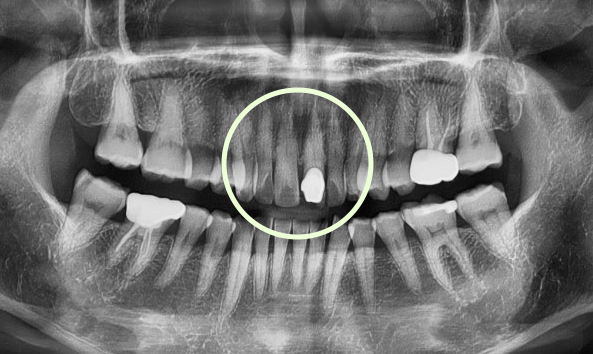

충치는 스스로 회복되지 않기 때문에,

정기적인 검진과 조기 치료가 건강한 치아를 오래 보존하는 가장 좋은 방법입니다.

지르코니아 크라운

고강도·고내구성, 어금니 포함 모든 부위 적용 가능